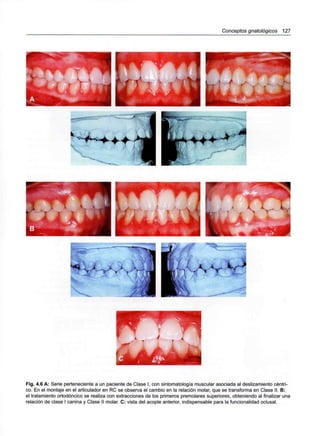

Capítulo 4 - Conceptos gnatológicos 119

Relación céntrica 122

Objetivos funcionales oclusales 124